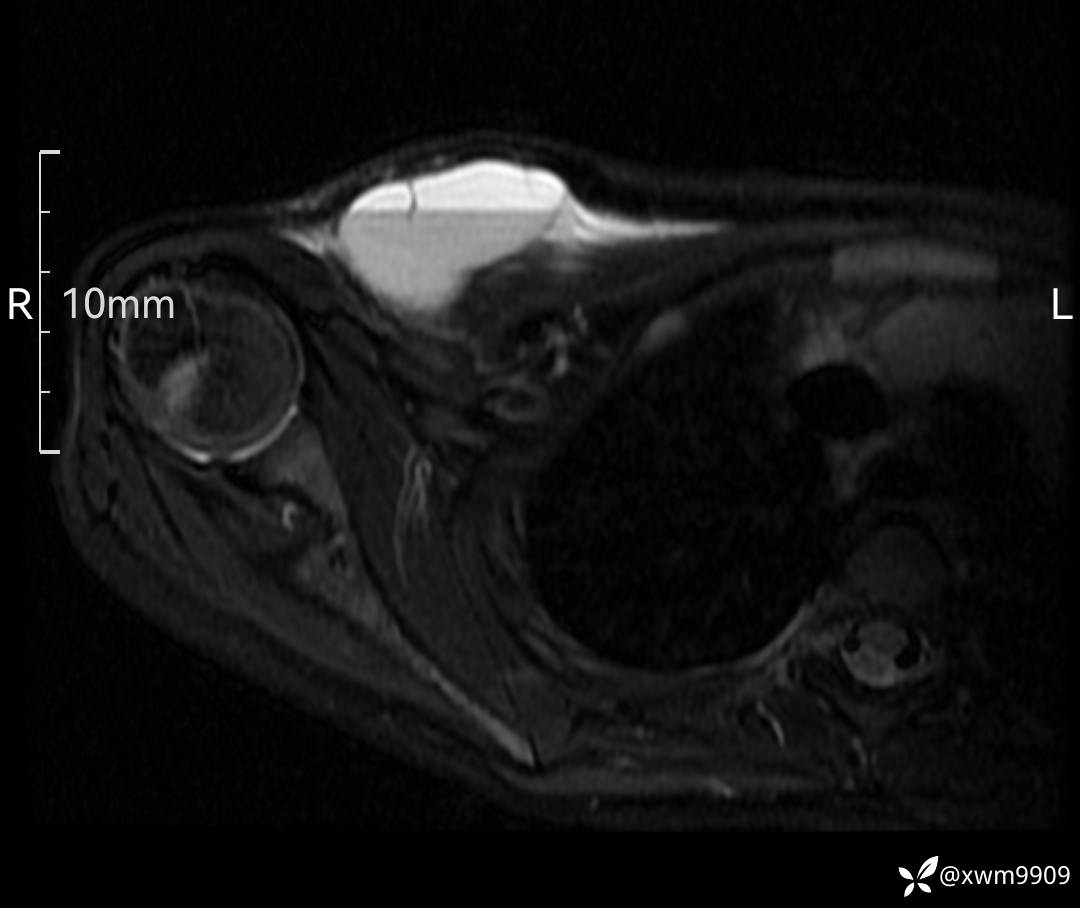

3、查体,右锁下方可及一约5x6Cm肿物,软丶边清丶未见明显发红,肤温不高,压痛明显,不可推动,稍有波动感。其他无特殊。

2、CT、MR肿块内可见液-液平面,常见有哪些疾病。